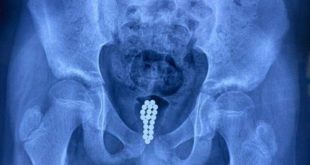

Menino que colocou 20 bolas no pênis passa por cirurgia de emergência

Um garoto de 11 anos sofreu com fortes dores por uma semana depois de colocar 20 bolas magnéticas no próprio pênis. Ele teve medo de contar aos pais sobre o acidente. A criança “curiosa” é de Dongguan, no sul da China, e precisou de cirurgia na bexiga para remover os brinquedos ...